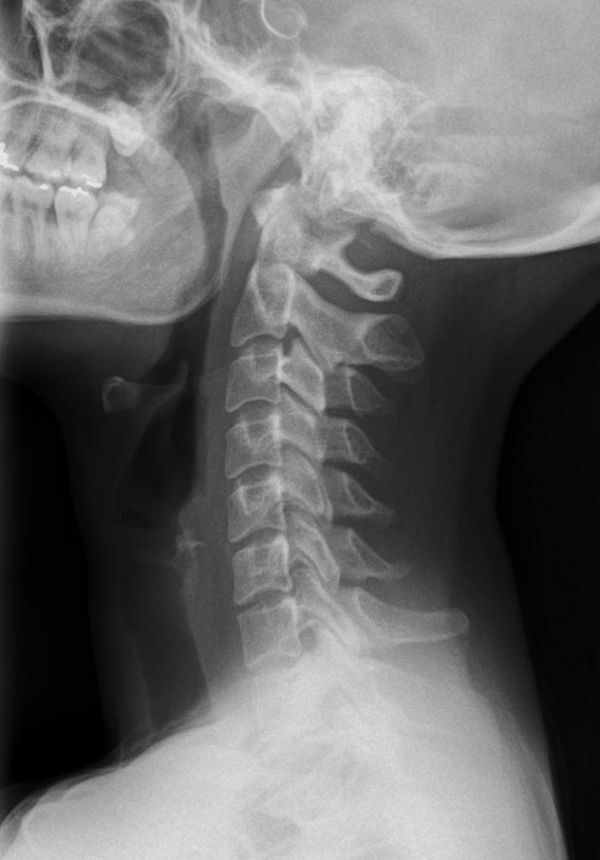

Röntgenaufnahme Halswirbelsäule

Die zu untersuchenden Anteile des Körpers werden meistens

in 2 unterschiedlichen Projektionsebenen dargestellt.

In einigen Körperregionen sind spezielle Zielaufnahmen notwendig.